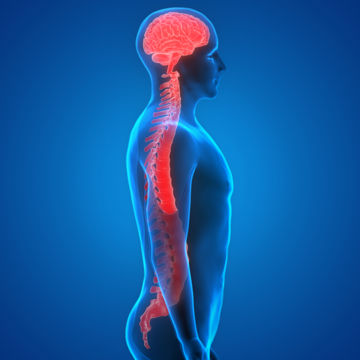

Multiple Sklerose (MS) ist eine nicht heilbare Erkrankung des zentralen Nervensystems (Gehirn und Rückenmark). Die Symptome sind von Mensch zu Mensch unterschiedlich.

Die neurogene Blase ist eine Erkrankung des unteren Harntrakts, die durch Schädigungen oder Erkrankungen des Nervensystems verursacht wird.

Multiple Sklerose (MS) ist eine nicht heilbare Erkrankung des zentralen Nervensystems (Gehirn und Rückenmark). Die Symptome sind von Mensch zu Mensch unterschiedlich.